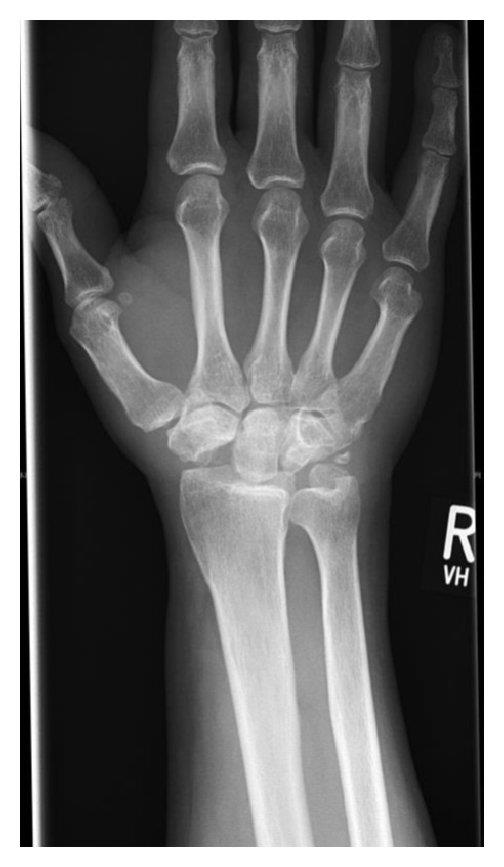

A 45-year-old male presents for evaluation of severe wrist pain. He has known scaphoid nonunion advanced collapse. He has failed nonsurgical measures and is requesting surgery. When considering a proximal row carpectomy, the presence of arthritis between which two carpal bones is a relative contraindication?

A proximal row carpectomy (PRC) procedure should be avoided if there are capitate head degenerative changes.

Shah et al. reviewed SLAC and SNAC injuries of the wrist. They reported that these injuries are the two most common patterns of posttraumatic wrist arthritis. They concluded that PRC is a reasonable treatment option for stage II and III SNAC, with potential disadvantages being a reduction of wrist motion and grip strength. They also state that this procedure should be avoided if there are capitate head degenerative changes.

Figure A is the unlabeled carpal bones of the wrist. Illustration A is the labeled carpal bones of the wrist. Illustration B is a postoperative radiograph of a PRC.

Answer 1, 2, 3, & 5: A PRC procedure should be avoided if there are capitate head degenerative changes, as evidenced by arthritis between the capitate and lunate. This procedure’s success is reliant upon normal cartilage/joint articulation of the capitate and lunate fossa of the distal radius.